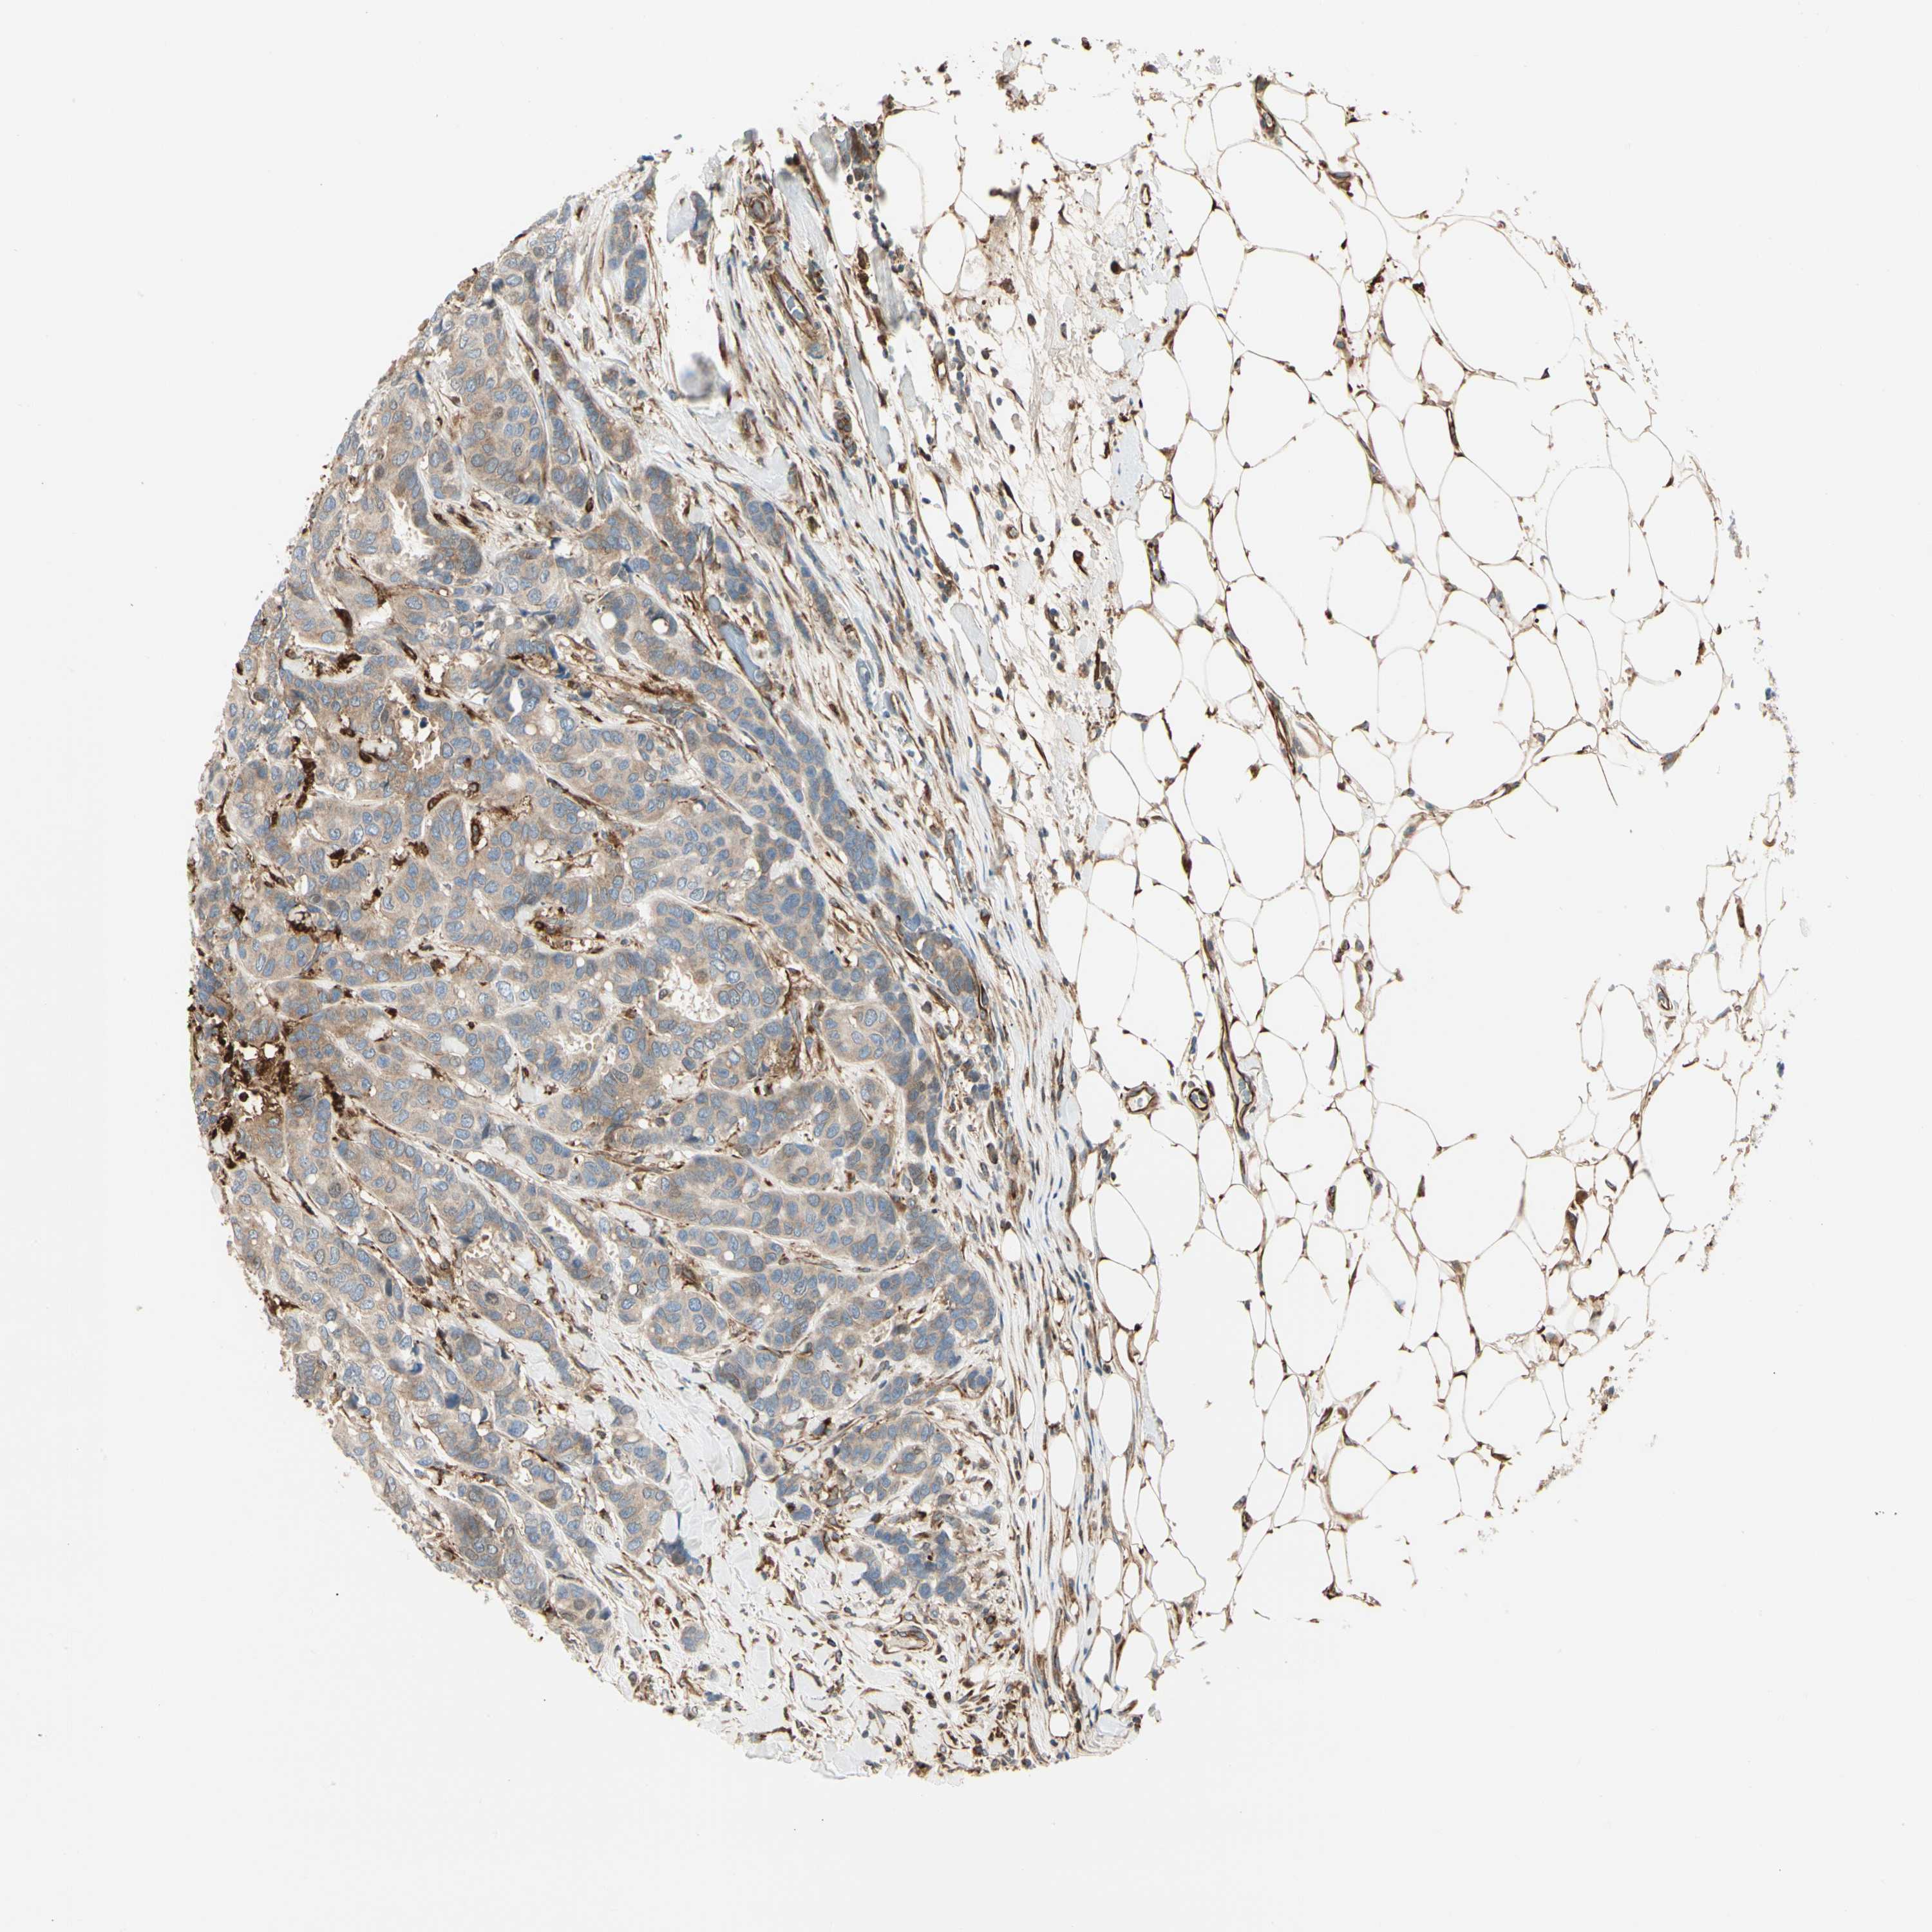

BRCA TCGA BRCA VALIDATION PROTEIN EXPRESSION